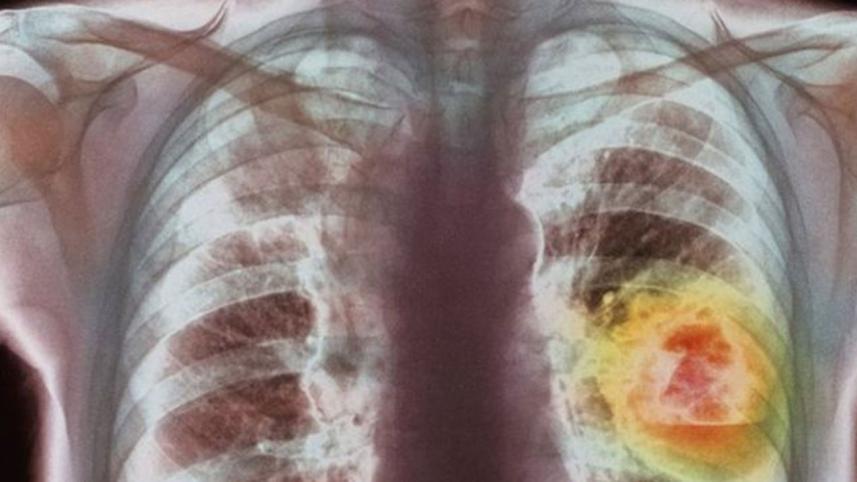

A lung cancer therapy can more than double life expectancy in some patients, a "milestone" trial shows.

Lung cancer is the most deadly type of cancer, killing nearly 1.6 million people every year.

It is hard to treat as it is often diagnosed late and many people with smoking-related diseases are unsuitable for surgery.